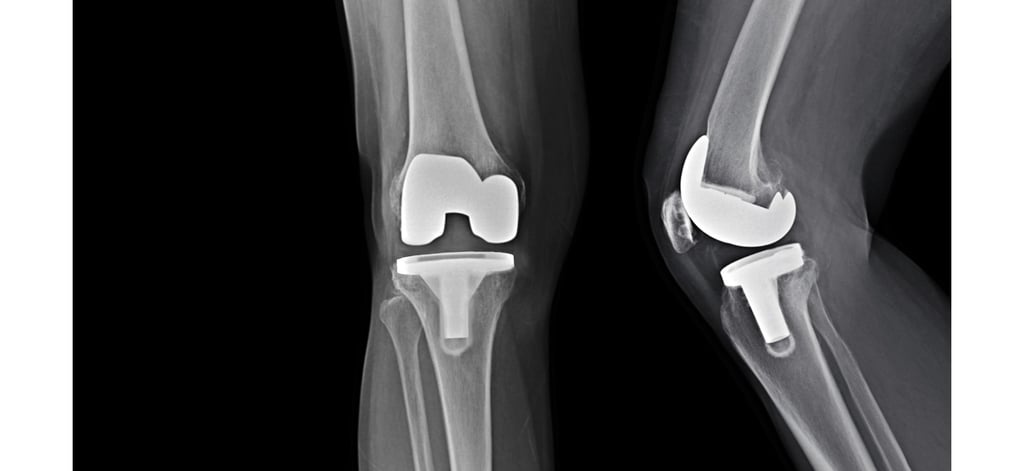

Guía sobre la Rehabilitación y Tratamiento de Fisioterapia para una Prótesis Total de Rodilla

La rehabilitación después de una cirugía de prótesis total de rodilla es crucial para garantizar una recuperación adecuada y el retorno a las actividades cotidianas. Este proceso no solo implica la mejora física, sino también un enfoque integral que abarca aspectos psicológicos y emocionales del paciente. En este artículo, exploraremos en profundidad el tratamiento de fisioterapia que acompaña a esta intervención quirúrgica.